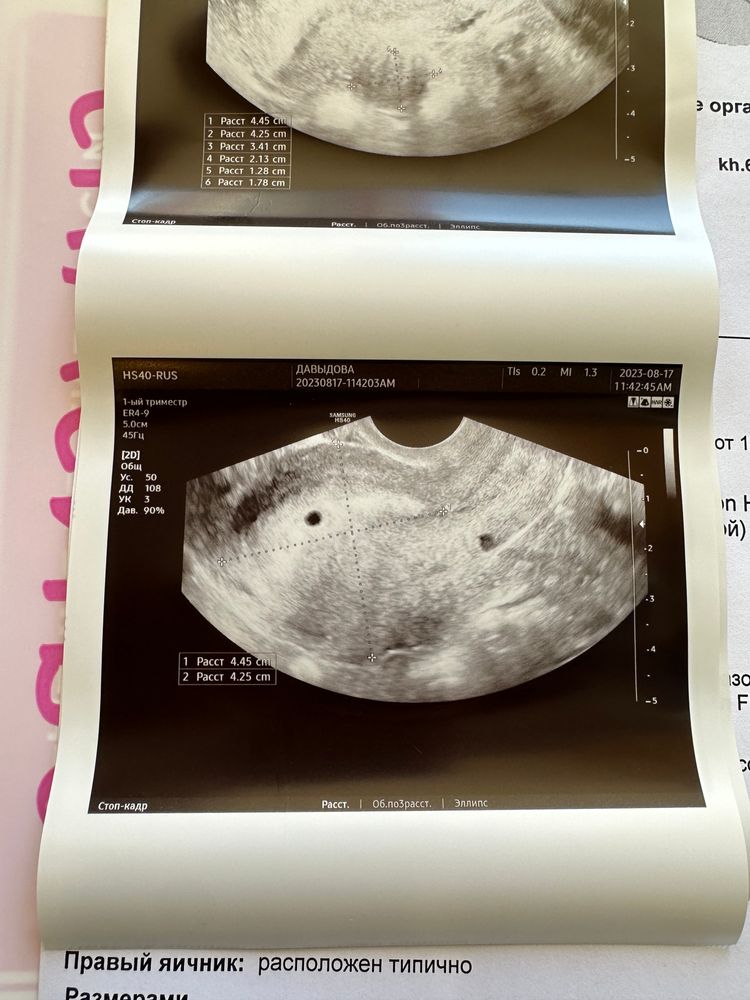

на 20 дпо (17.08) ходила на узи, нашли пя в матке, сказали, что все хорошо